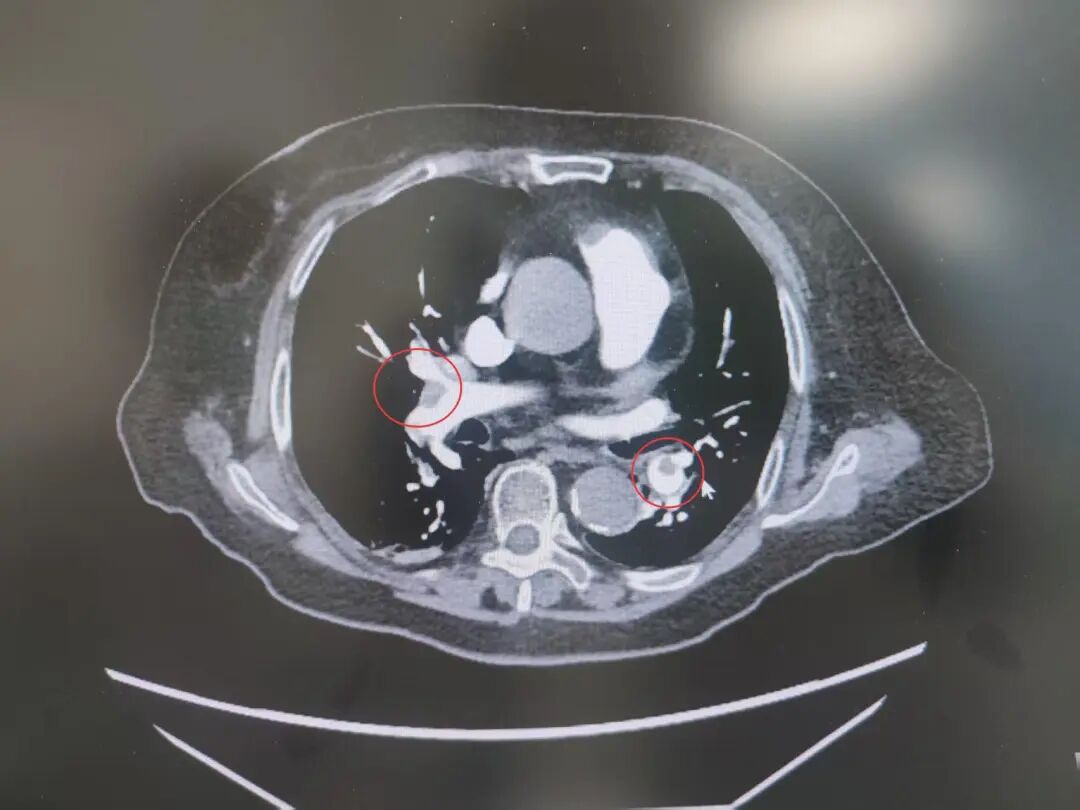

患者高血压病史7年,最高血压达190/100mmHg,2型糖尿病7年,控制不佳。发病前3天,意外摔伤致股骨颈骨折,后出现咳嗽、呼吸困难、胸痛等症状,被紧急送到我院急诊。完善相关检查后,明确诊断为中高危肺栓塞——这是一种足以危及生命的急症,病情进展迅速。

肺栓塞

肺占位

为进一步精准救治,呼吸与危重症医学科宋刚主任带领团队对患者进行全面评估,结果令人揪心:肺血栓栓塞(中高危)、I型呼吸衰竭、肺占位性病变、急性冠脉综合征、急性肾功能不全、肝功能不全、脓毒症等多种疾病,且随机血糖高达31.68mmol/L,远超正常范围,生命体征岌岌可危。